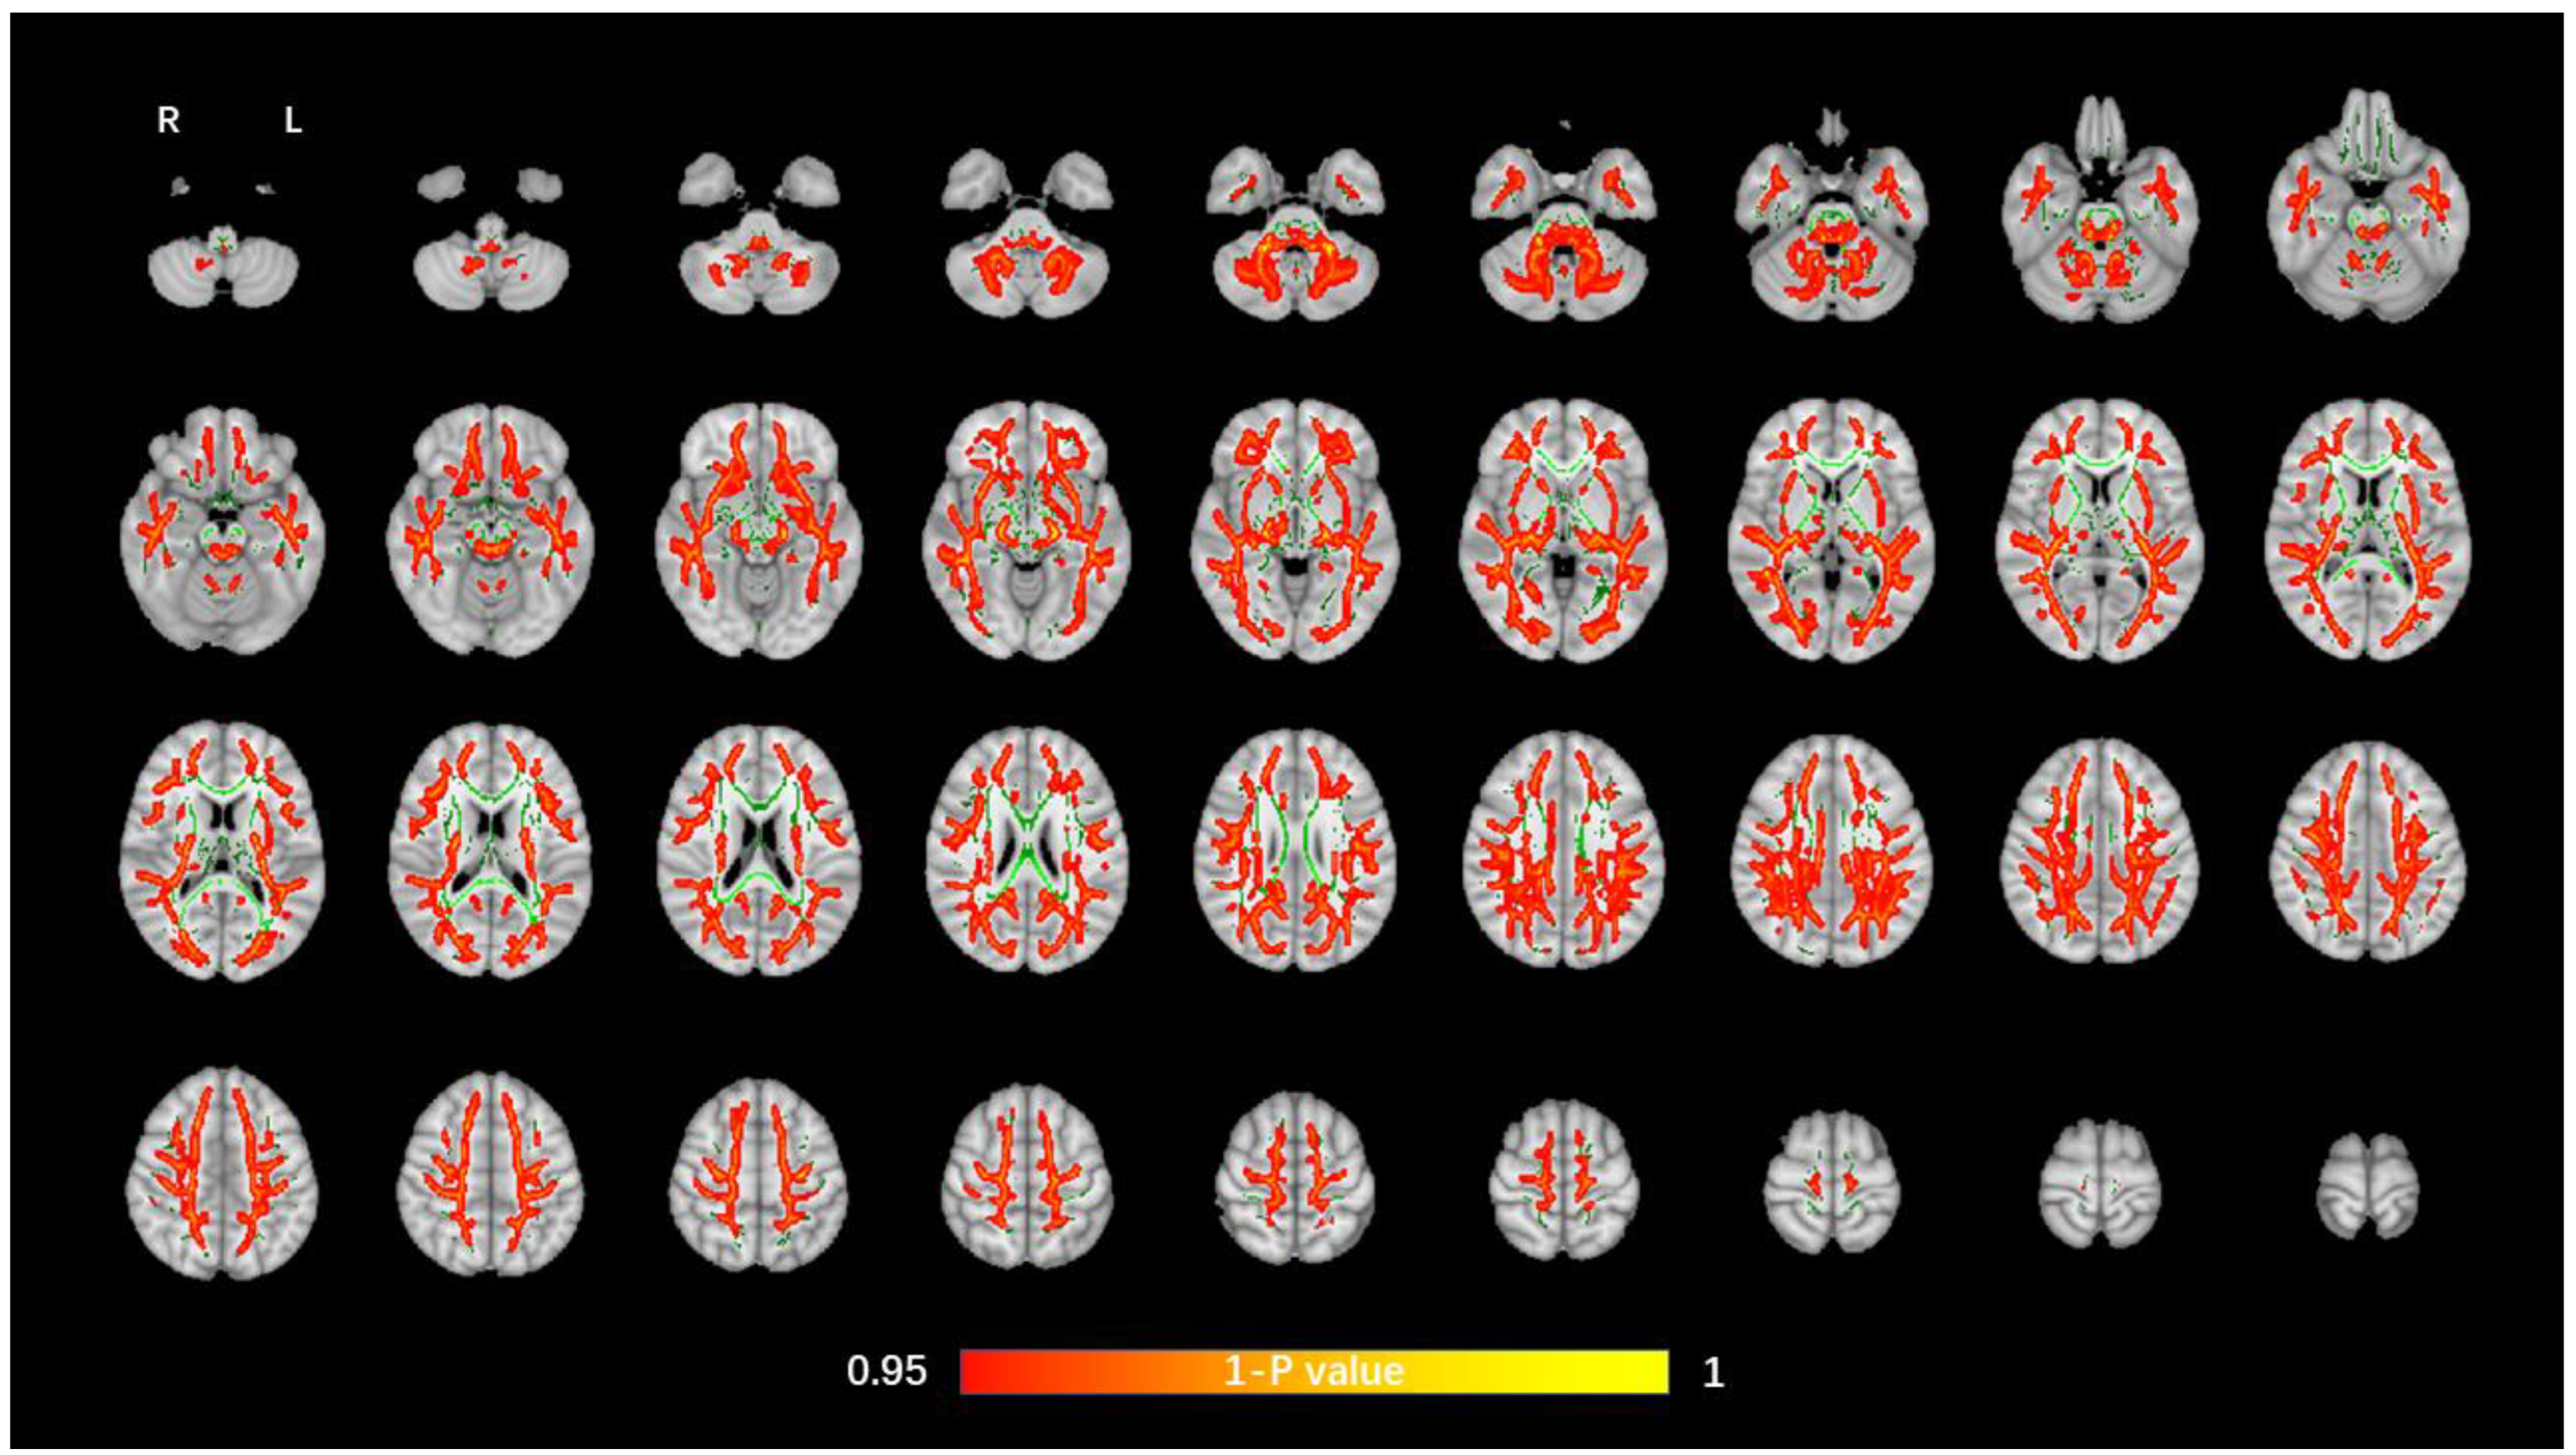

3.2. TBSS Analysis of DTI Data